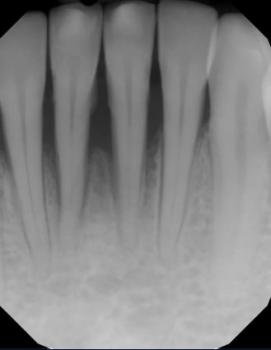

A periapical lesion is a radiolucent area at the tip of a tooth’s root, usually caused by pulp necrosis, infection, or chronic inflammatory breakdown of bone. Managing such a lesion requires accurate diagnosis, a step-by-step endodontic protocol, and a well-monitored healing timeline. The diagram provided visually represents the modern clinical sequence of removing infected pulp, shaping and disinfecting the canal, and sealing the root system to stop infection and allow bone regeneration.

Radiographic Findings

A periapical radiolucency typically shows:

Breakdown of lamina dura

Dark circular or irregular area at the root apex

Loss of trabecular bone pattern

Widened periodontal ligament space